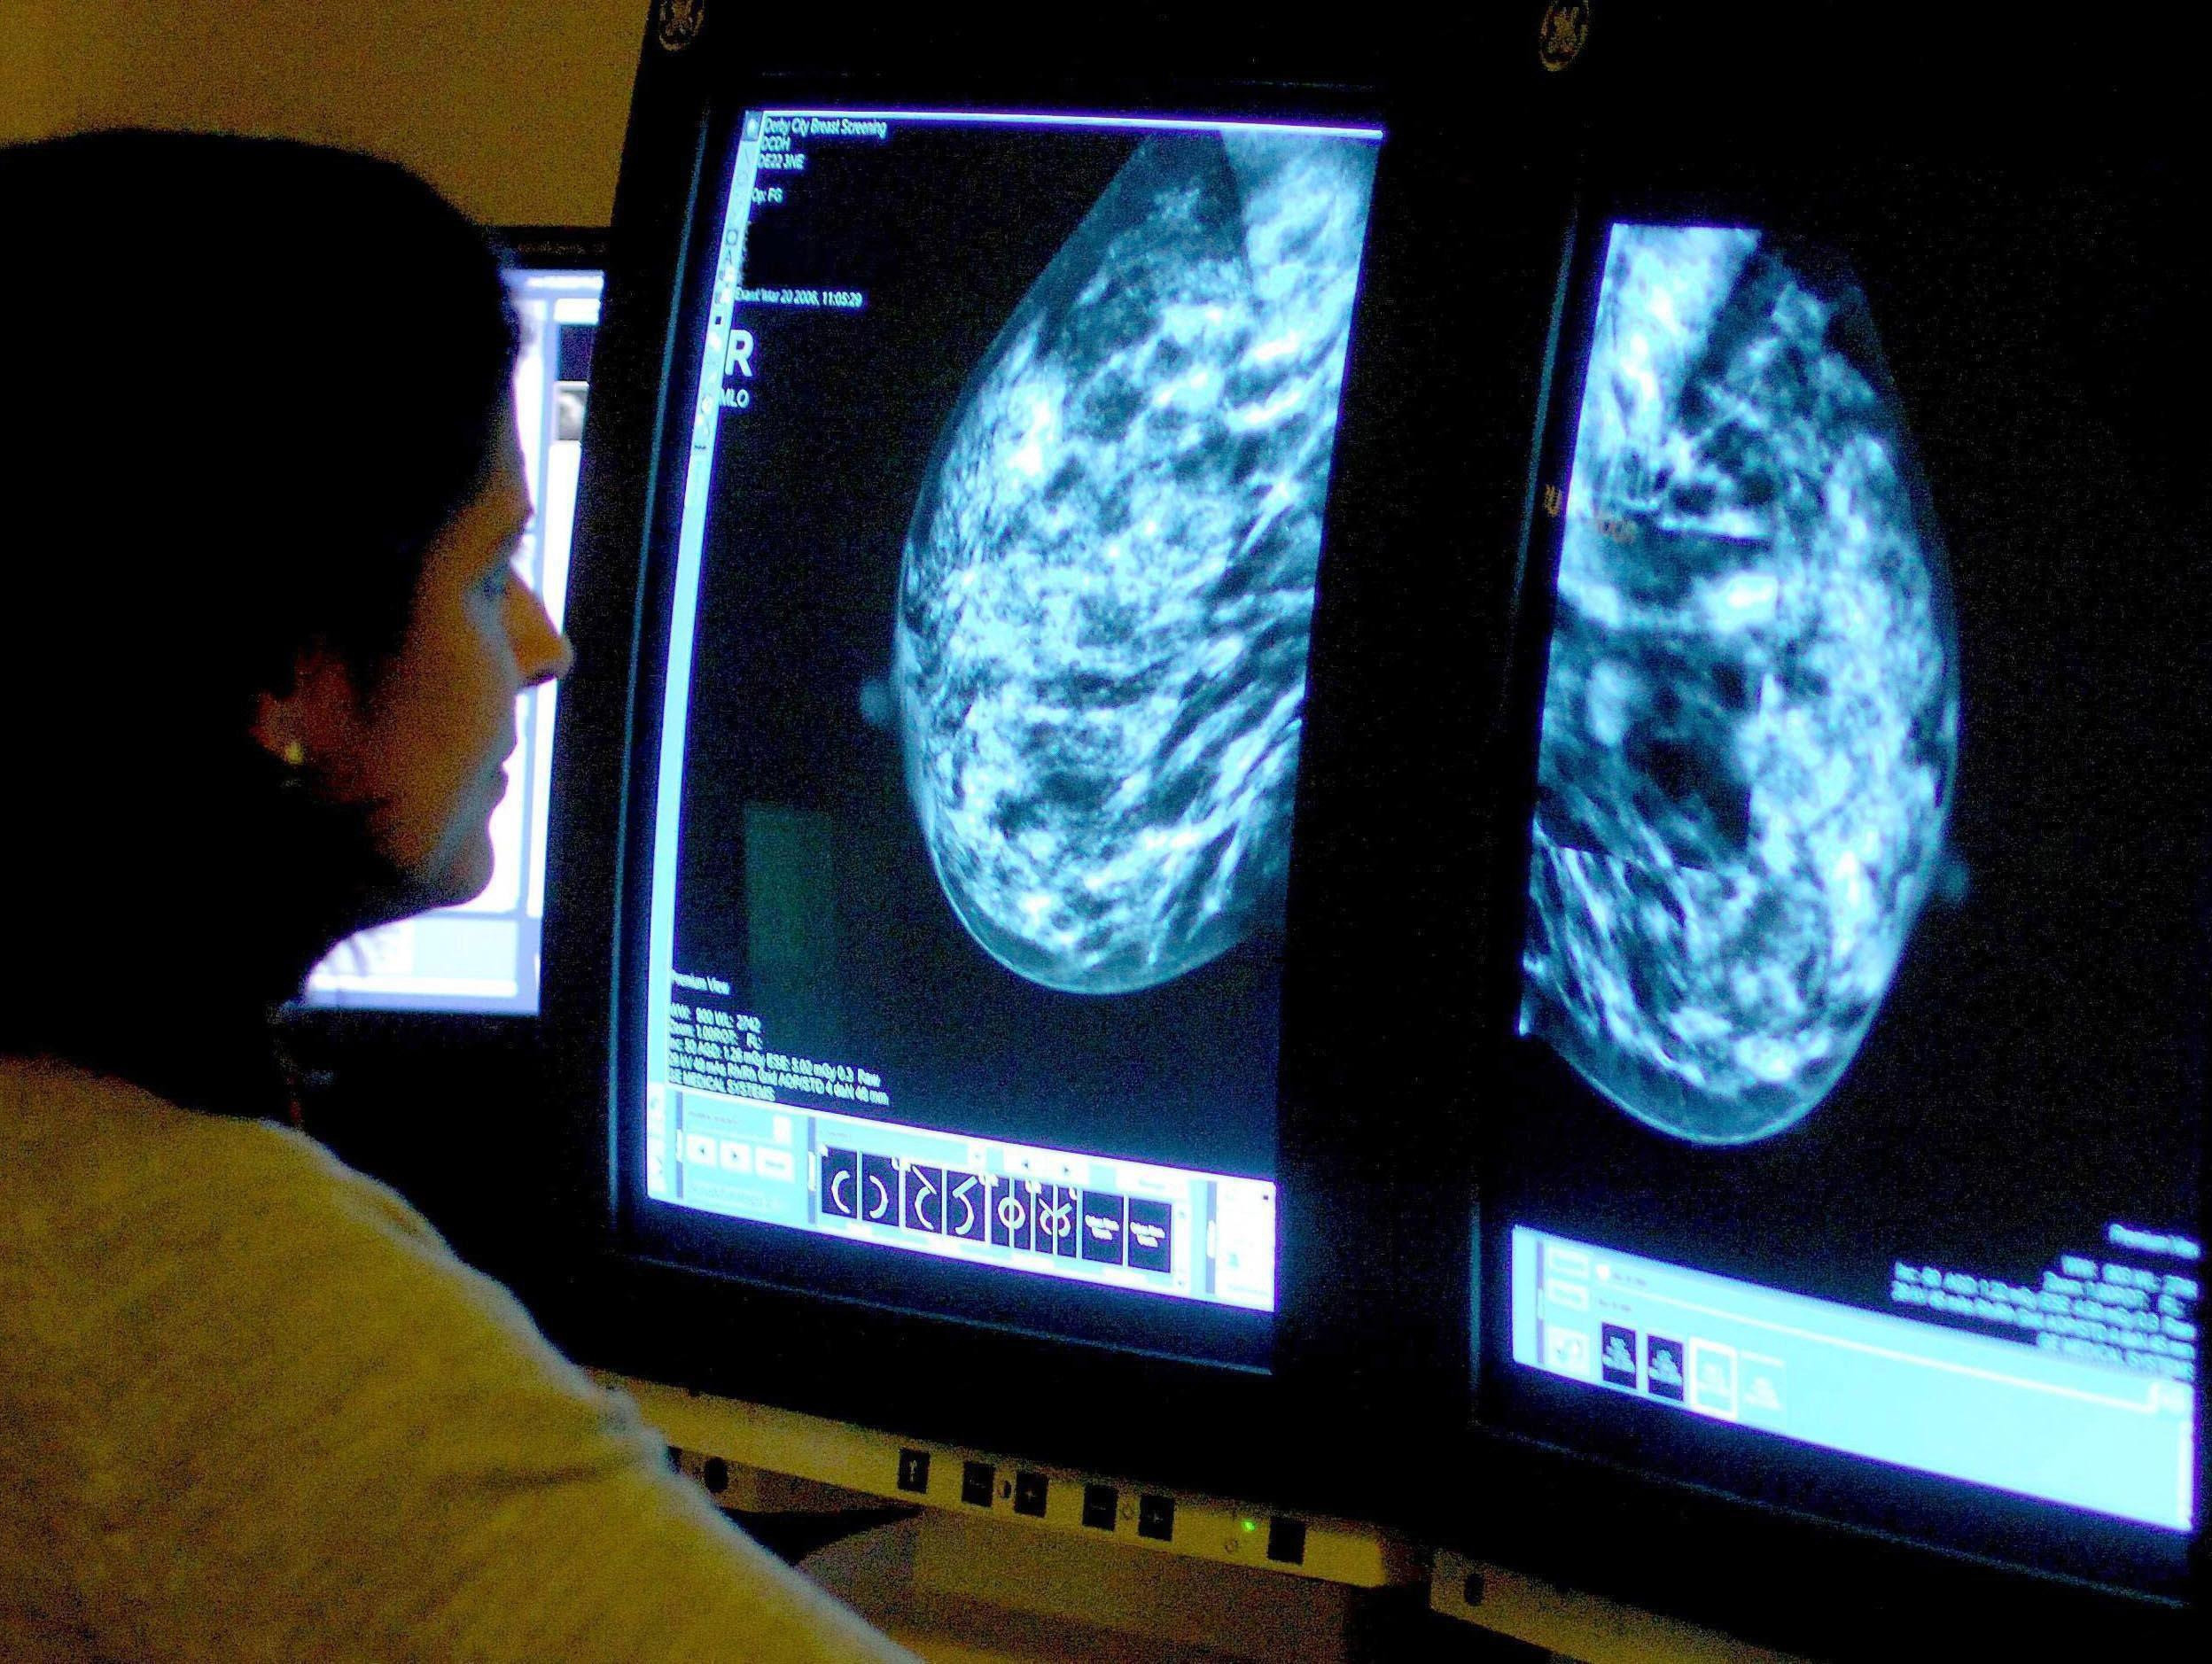

At the appointments, x-rays known as mammograms are taken to look for cancers that are too small to see or feel.

At the moment, two radiologists are required to review the images from each screening to ensure accuracy.

However, it is hoped the AI being trialled will enable one to complete the process, freeing up radiologists to see more patients and, in turn, cut waiting lists.